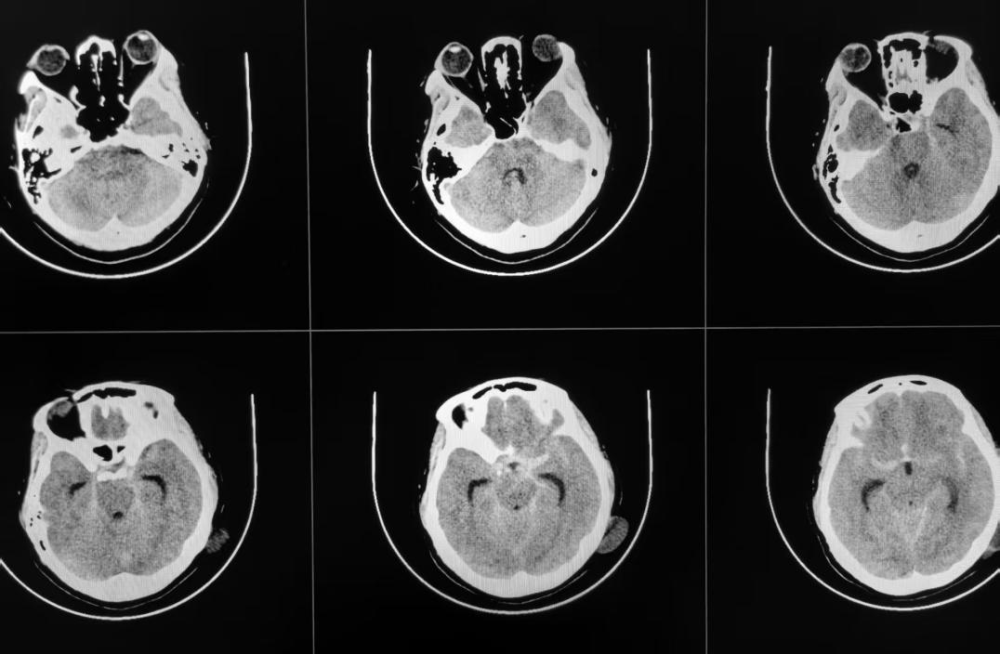

术前CT提示蛛网膜下腔出血

王女士(化名)因突发头痛伴恶心、呕吐5小时被紧急送往我院就诊,入院时症状不断加重,意识逐渐模糊,且频繁恶心、呕吐,急诊头颅CT检查显示蛛网膜下腔出血。脑科医院院长纪文军主任医师接诊后,立即启动卒中绿色通道。经详细问诊,得知王女士有多年的肾病综合征及高血压病史,且血压一直居高不下,动脉瘤破裂风险极高。纪文军主任医师判断情况危急,立即安排脑血管检查进一步明确诊断。

在肾病内科协助制定肾功能保护方案后,紧急完成全脑血管造影,确诊为"左侧颈内动脉眼动脉段血泡样动脉瘤"。因该类动脉瘤形态特殊,传统开颅夹闭难度大,而常规介入栓塞易复发且术中易破裂,纪文军主任医师凭借丰富的经验和对前沿技术的掌握,最终决定采用国内领先的"密网支架(血流导向装置)联合弹簧圈栓塞"术。